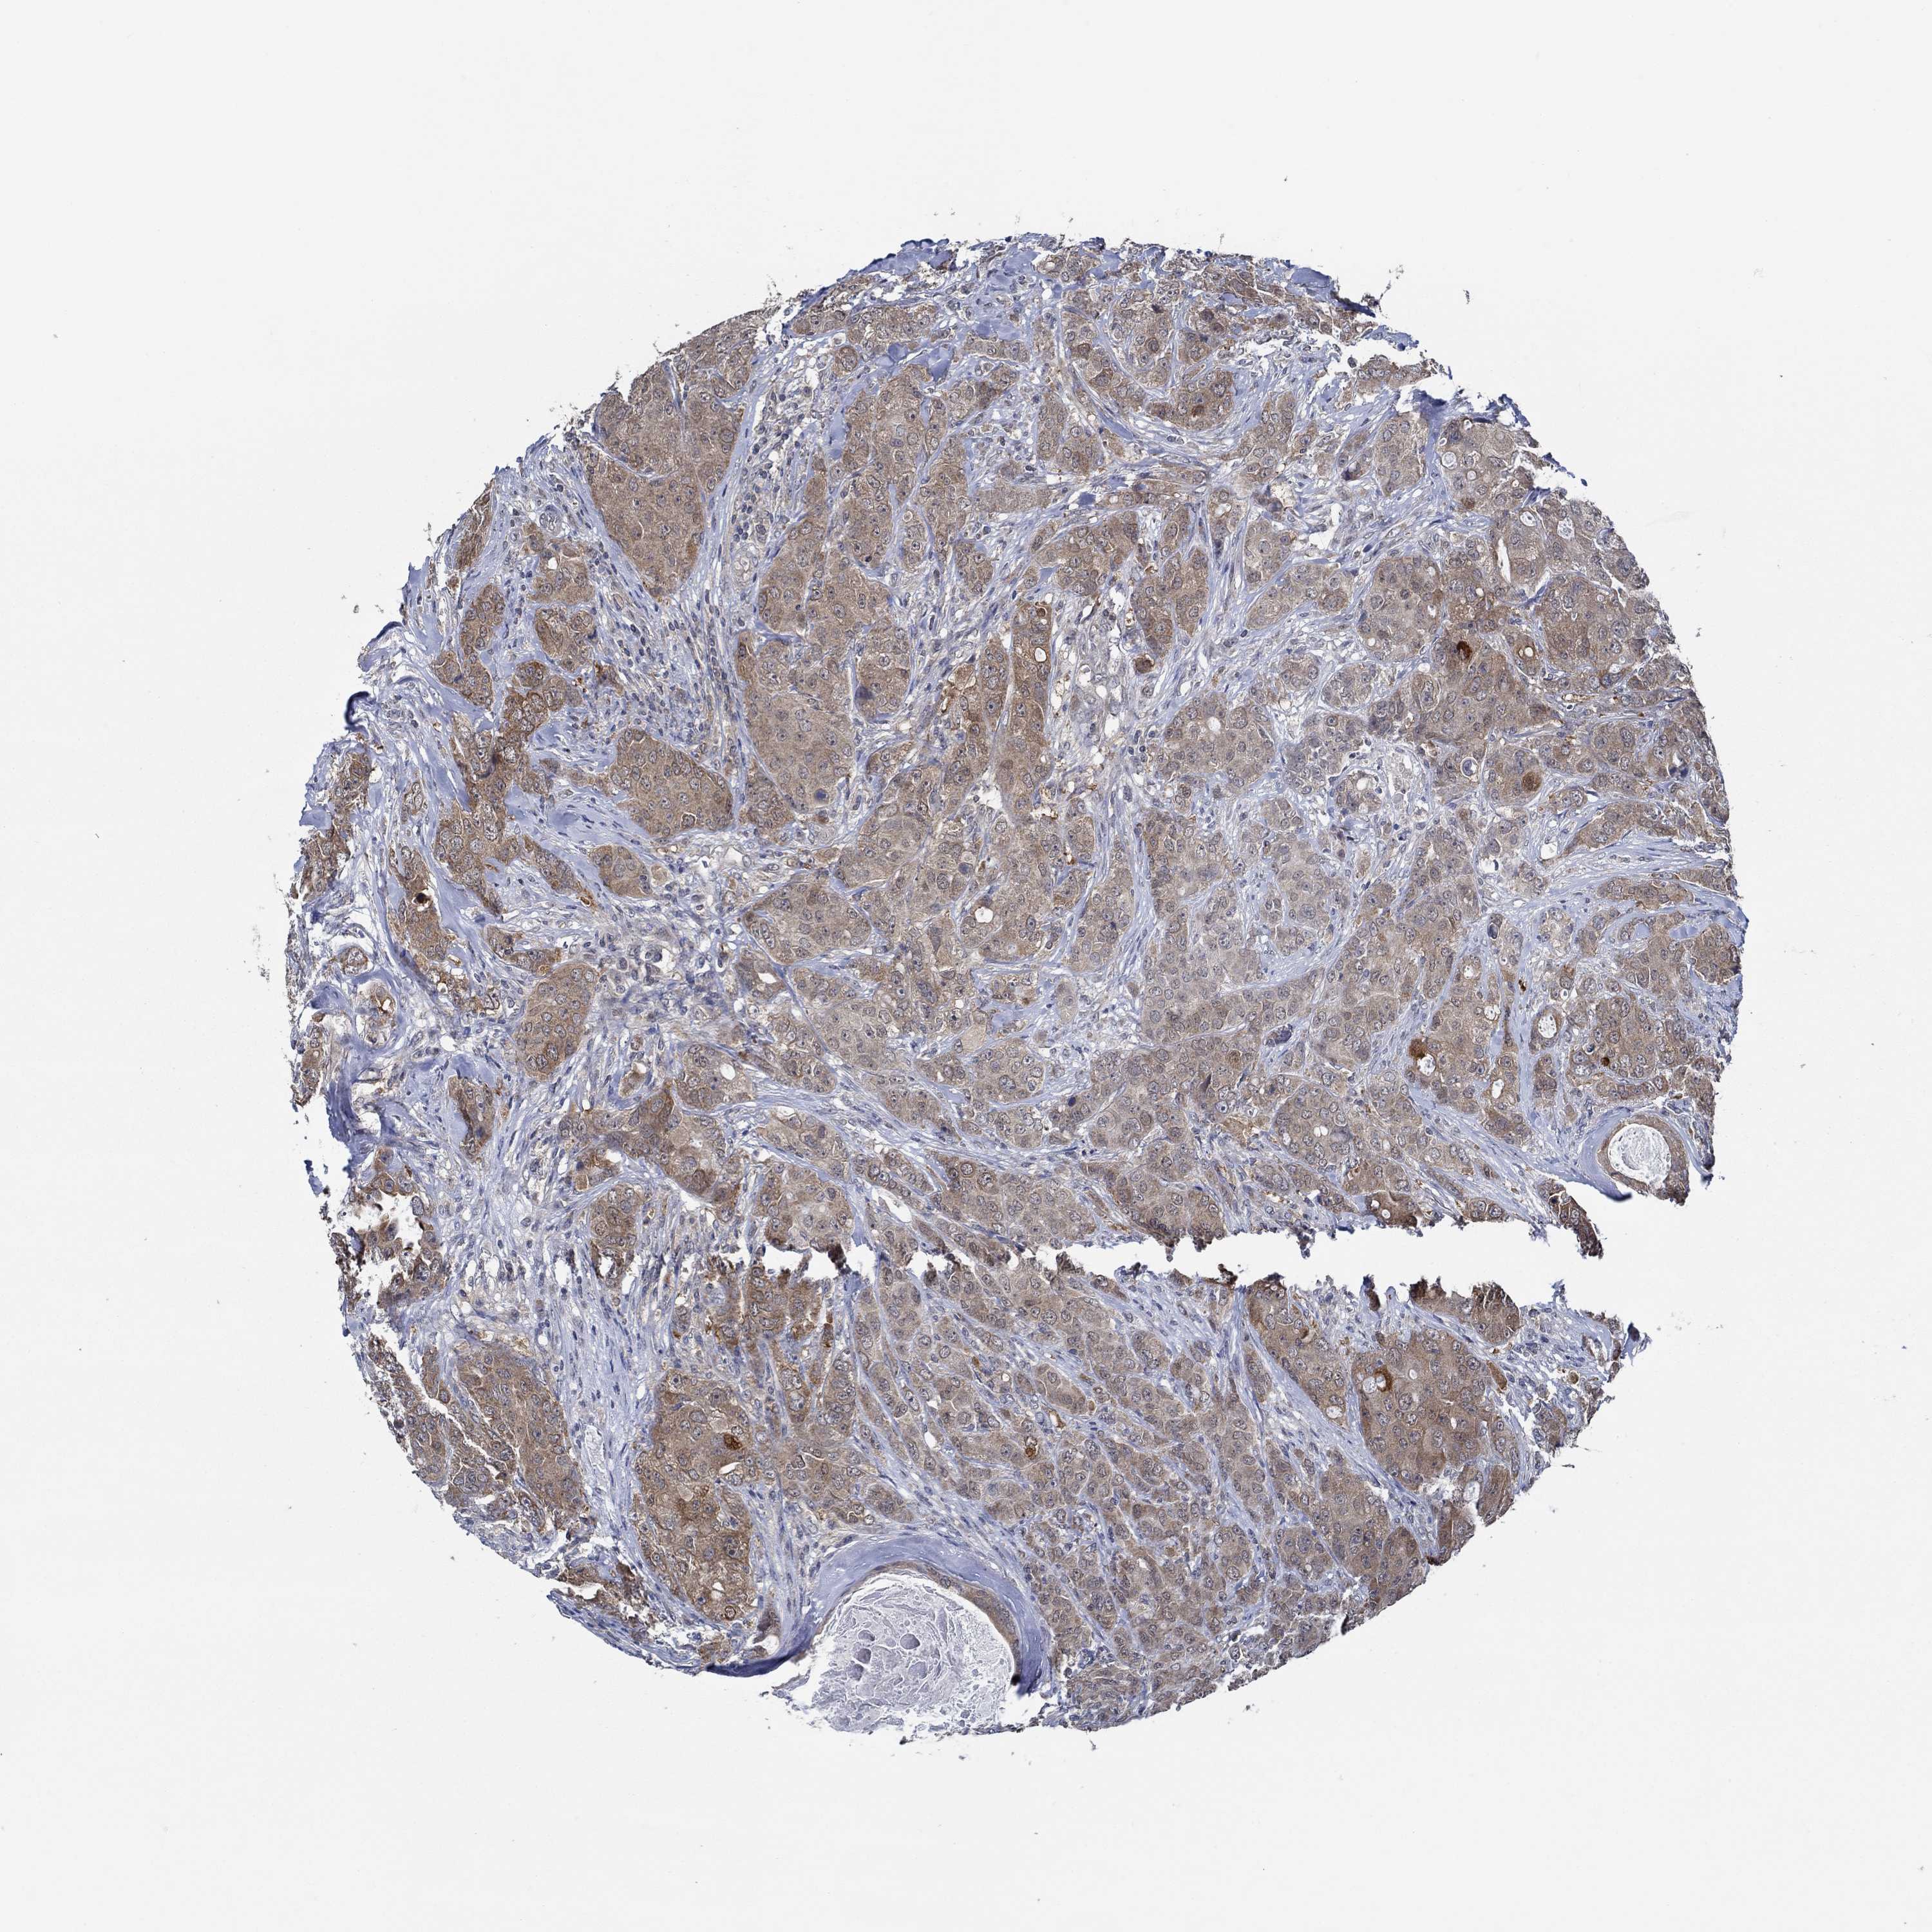

BRCA TCGA BRCA VALIDATION PROTEIN EXPRESSION

ANTIBODIES

AND

VALIDATION